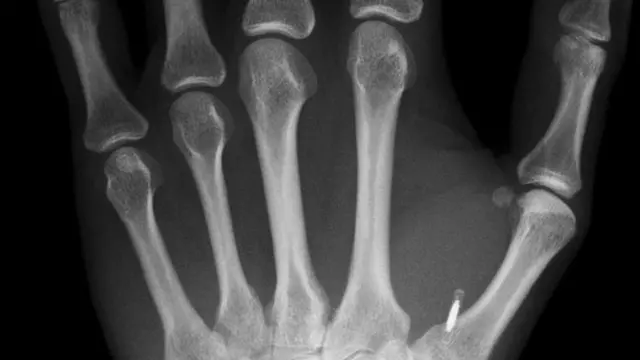

Mal dá para perceber a pequena elevação nas costas da mão de Dave Williams - a maioria das pessoas não veria de primeira o calombo do tamanho de um grão de arroz entre seu dedão e o indicador.

Sob a pele de Williams há um implante de microchip - um circuito eletrônico dentro de uma cápsula de vidro em formato de pílula - que pode ser usado da mesma forma que um cartão de crédito sem contato.

Dave Williams não se preocupa com as questões de vigilância do chip em sua mão, já que ele só pode ser ativado a poucos centímetros de um leitor. "Ter medo de uma perseguição estilo GPS é basicamente ficção científica neste momento", afirma. Williams também gosta de enfatizar que o procedimento de implantação não é tão terrível, como alguns podem imaginar.

Williams instalou o chip sozinho usando muito iodo, para deixar tudo esterilizado. "Quase não senti dor", diz ele. "Tirar a identificação será um pouco mais difícil, mas não dá tanto trabalho com um bisturi e um par de pinças."